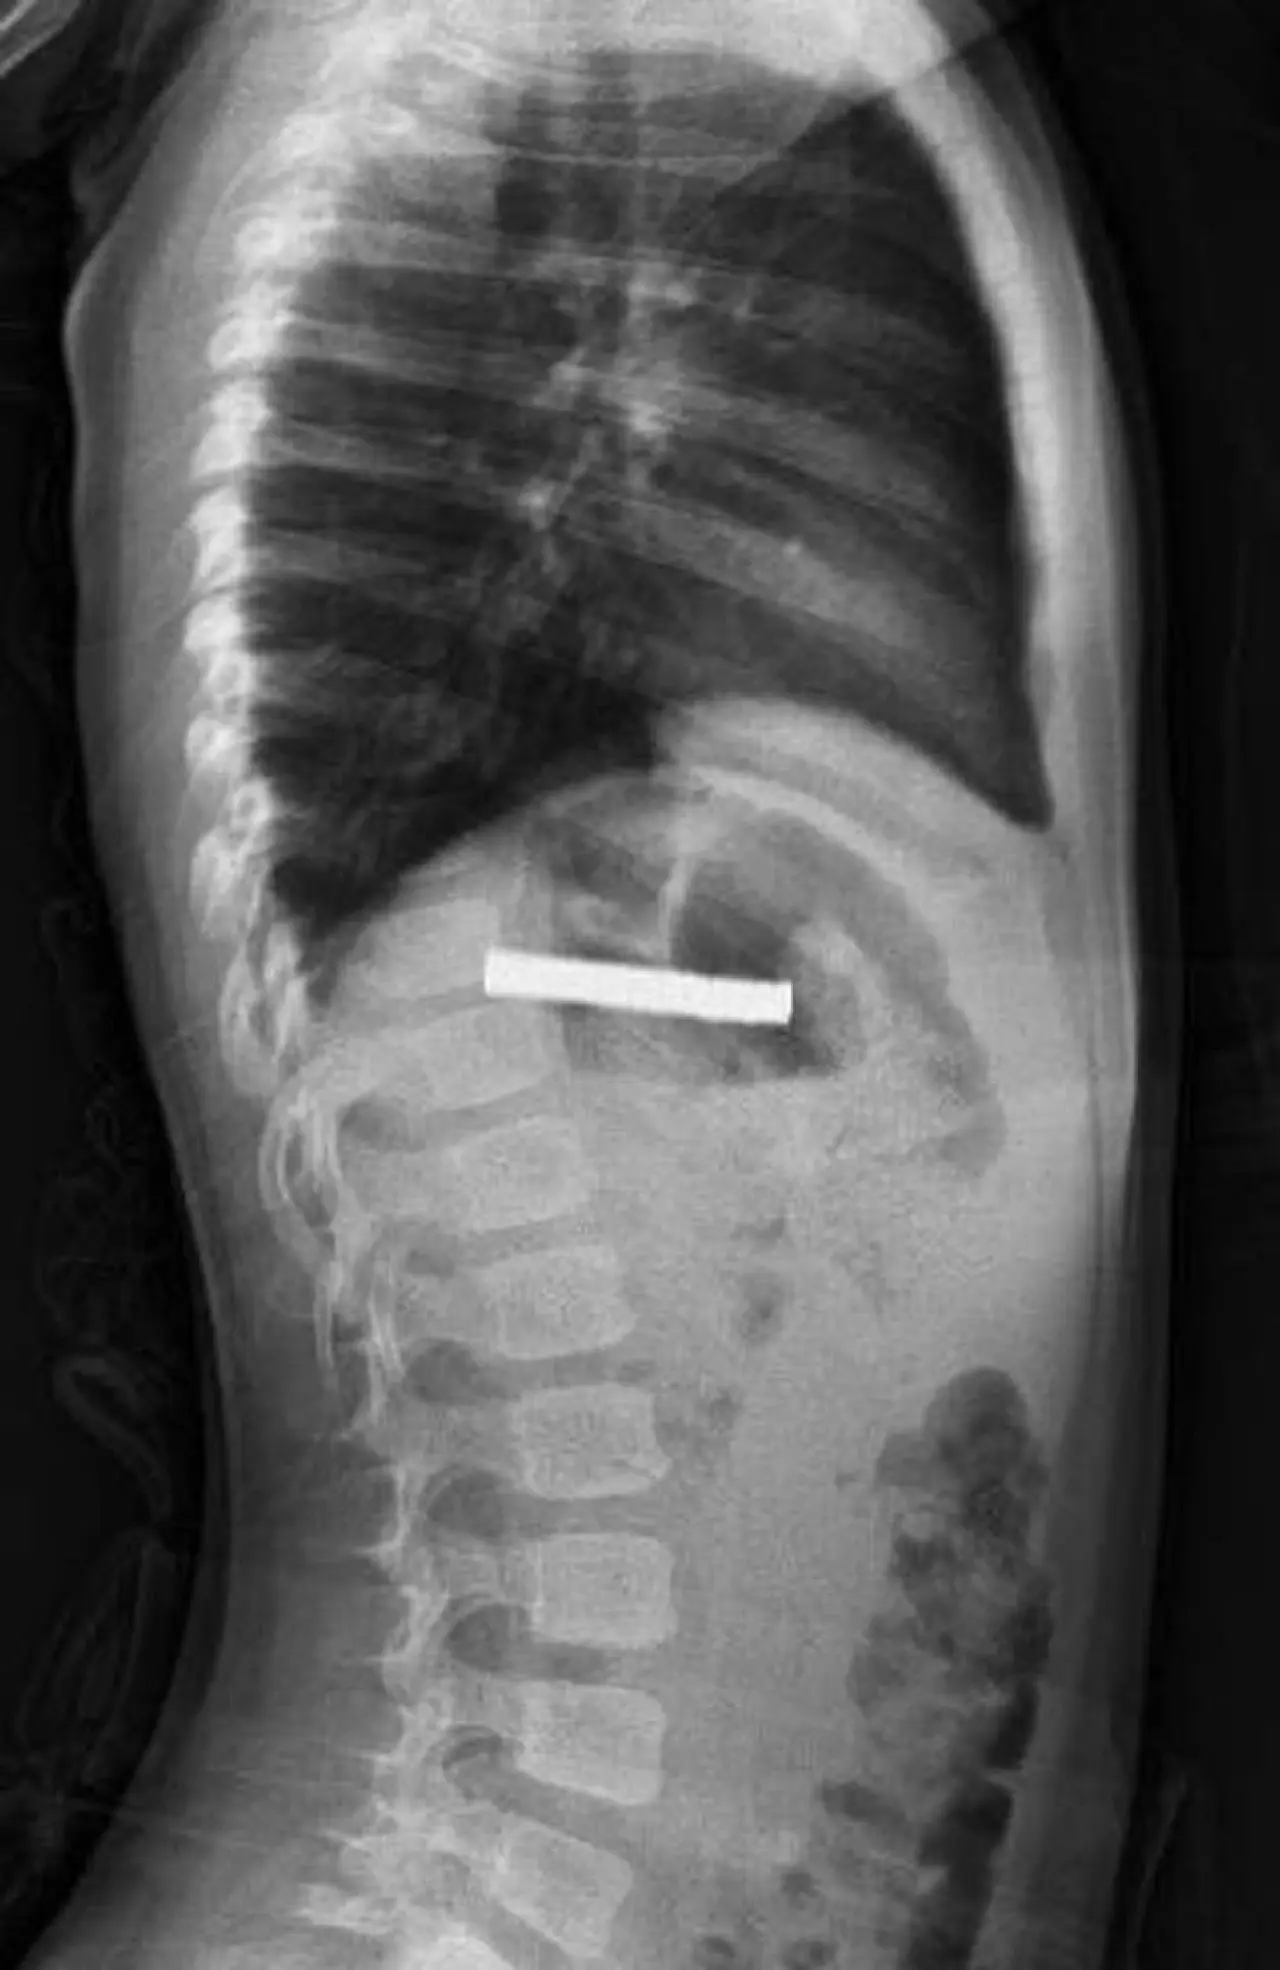

Elazığ'da 3 yaşındaki bir çocuğun yuttuğu 19 mıknatıs başarılı bir operasyonla çıkarıldı.

Fırat Üniversitesi Hastanesi'nde endoskopik yöntemle mıknatıslar çıkarıldı. Mıknatıslar yemek borusuna zarar verdi.